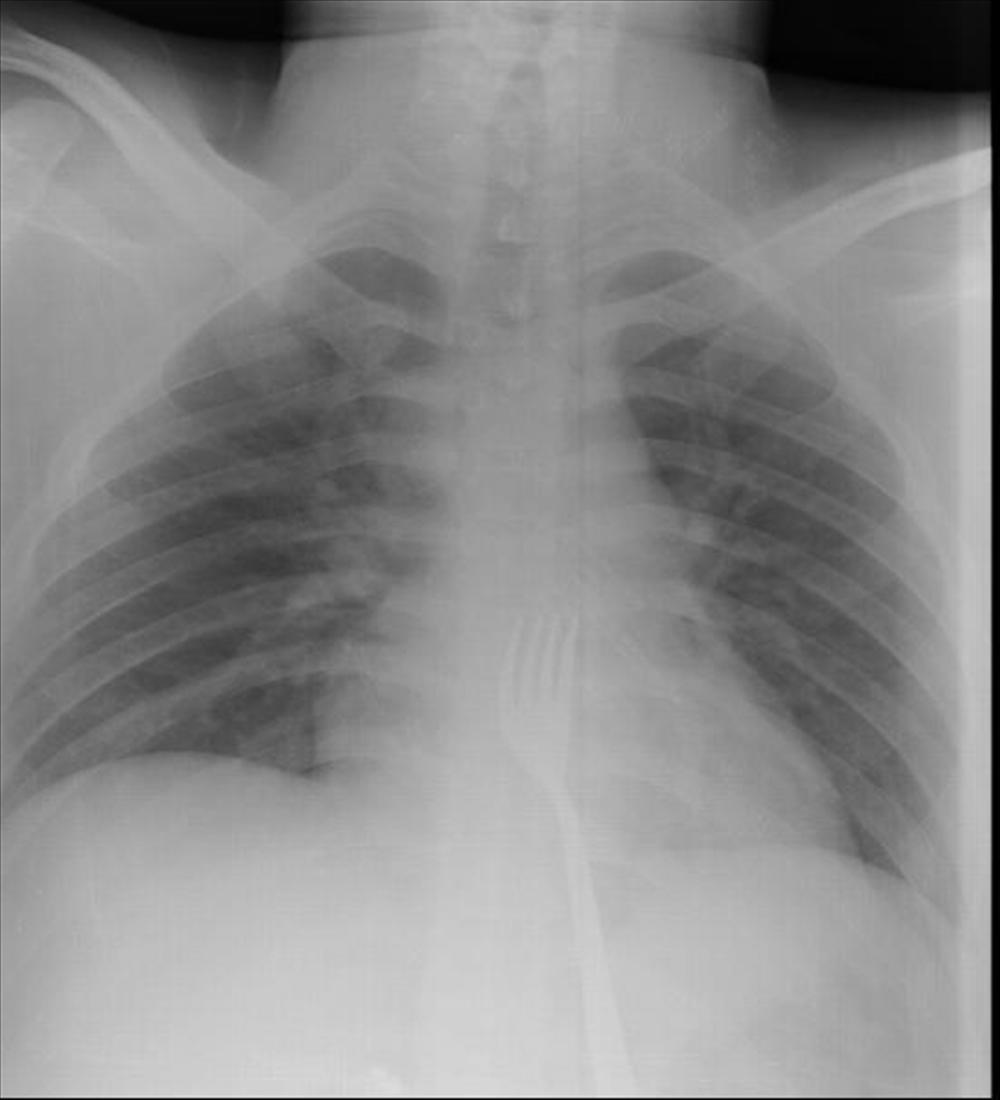

Na snimku je uočena metalna viljuška duga 15 centimetara, koju su lekari potom odstranili iz tela.